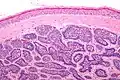

Dermal cylindroma. Puzzle-like distribution of tumour foci.

Dermal cylindromas are:

- Dermal lesions consisting of nests of cells that are surrounded by hyaline (i.e., glassy, eosinophilic, acellular) material and have:

- Hyperchromatic nuclei that may palisade (columnar nuclei arranged around the periphery of the cell nests with their short axis tangential to the nest periphery), and

- Cells with lighter staining ovoid nuclei at their centre.